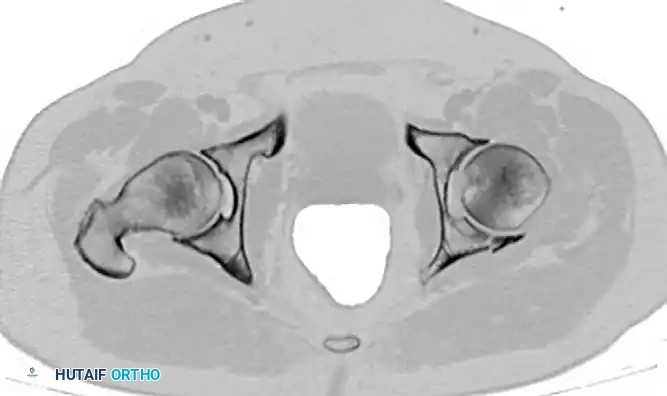

Secondary Congruence in Both-Column Fractures

A unique phenomenon observed exclusively in both-column fractures is "secondary congruence." Because all articular fragments are detached from the axial skeleton, they can occasionally settle concentrically around the medially displaced femoral head.

If the articular cartilage space is preserved and the femoral head remains concentrically enveloped by the fragments (despite medialization of the entire joint complex), nonoperative treatment via skeletal traction can yield surprisingly excellent long-term functional results.